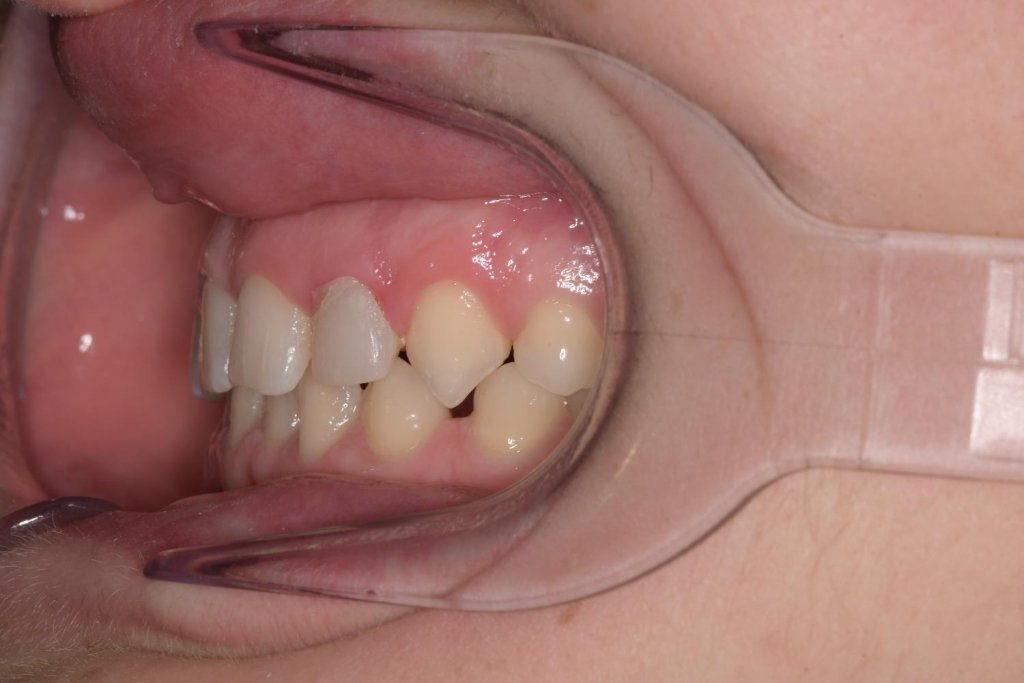

Tras 12 meses de ortodoncia, llevada a cabo por mi colega la Dra. Celia Pisonero (un bravo por ella), conseguimos nuestro objetivo:

Esto es el resultado después de la ortodoncia, no os dejéis engañar por la gingivitis de los inferiores, es tras la retirada.